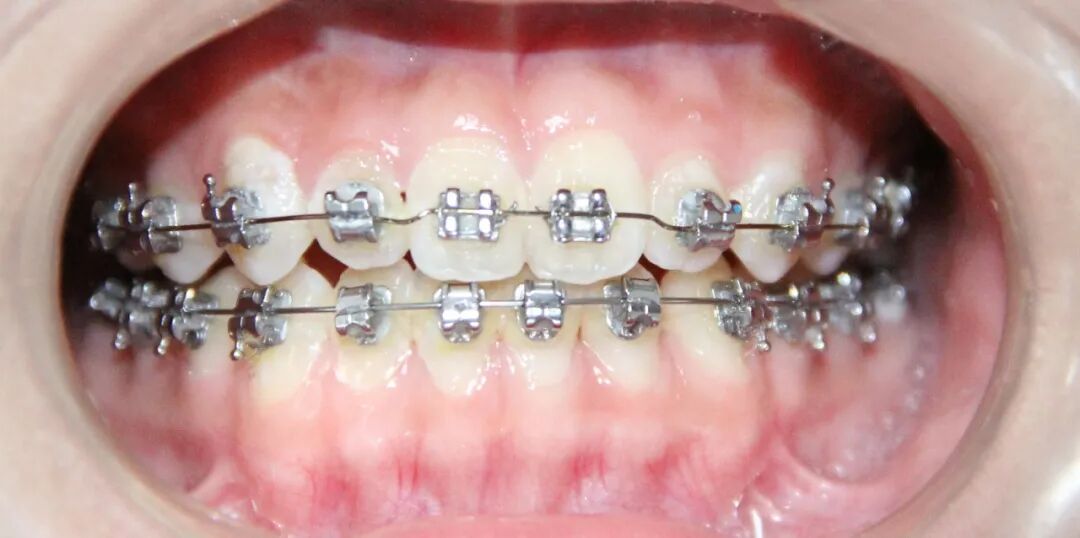

病例2

治疗后